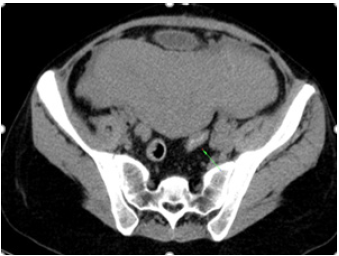

After excluding possible causes of acute abdomen, the patient underwent intravenous contrast-enhanced computed tomography (CT) that demonstrated left ovarian vein repletion defect compatible with the presence of a thrombus (Figure 1&2). Blood cultures were positive for Escherichia coli. The patient started treatment with enoxaparin and intravenous antibiotic therapy for 5 days. She was discharged on the 10th postpartum day. It was recommended to continue enoxaparin for at least three months, with outpatient follow-up with hematology.

Figure 1: Coronal Demonstrates (CT) an enlarged ovarian vein with central hypodensity, representing thrombosis (arrow).

Figure 2: Abdominal CT scan-arrow showing thrombosed right ovarian vein.